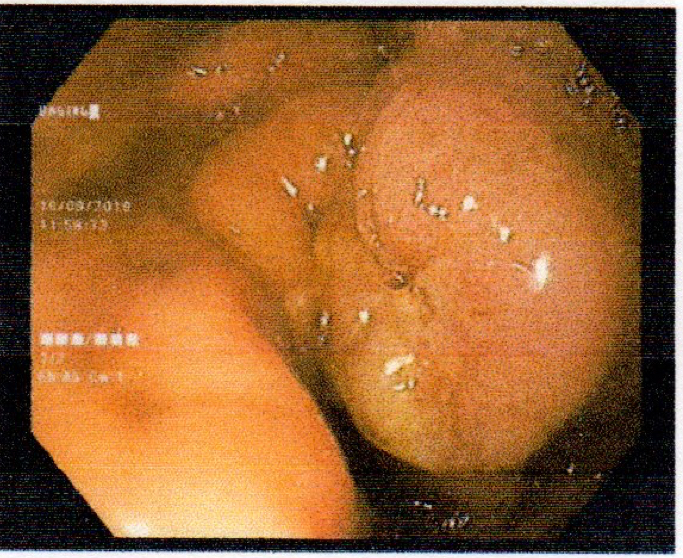

Gastric abnormalities show nonspecific gastrointestinal symptoms and similarly radiological findings. Intra and extra luminal gastric wall thickening are the most common finding in benign and malignant pathologic process. This aim of this case report was to describe several characteristics such as the location and size of the lesion, involvement of the gastric wall and surrounding structures, calcifications, and contrast enhancement pattern which can assist in radiological diagnosis. Several cases at our institution have similar gastrointestinal complaints, however, there were different lesions characteristic found in contrast enhanced abdominal CT scan. The first case 72-years-old man experienced hematemesis with radiologic finding diffuse gastric mucosal thickening as well as homogenous contrast enhancement but without calcification. The second case 37-years-old man complaint dizziness and melena with radiologic finding large tumor more than 10 cm in size, amorph calcification and heterogenous contrast enhancement. The last 60-years-old man case experienced melena and hematemesis, from abdominal CT scan showed irregular gastric mucosal thickening with heterogenous contrast enhancement and fat stranding around the lesion, without calcification. Methods used in these cases were contrast-enhanced abdominal CT scan, esophagogastroduodenoscopy (EGD), and biopsy in order to determine the diagnosis. Contrast-enhanced abdominal CT scan plays a vital role in describing the lesion characteristics which affects the determination of treatment options and future prognosis.